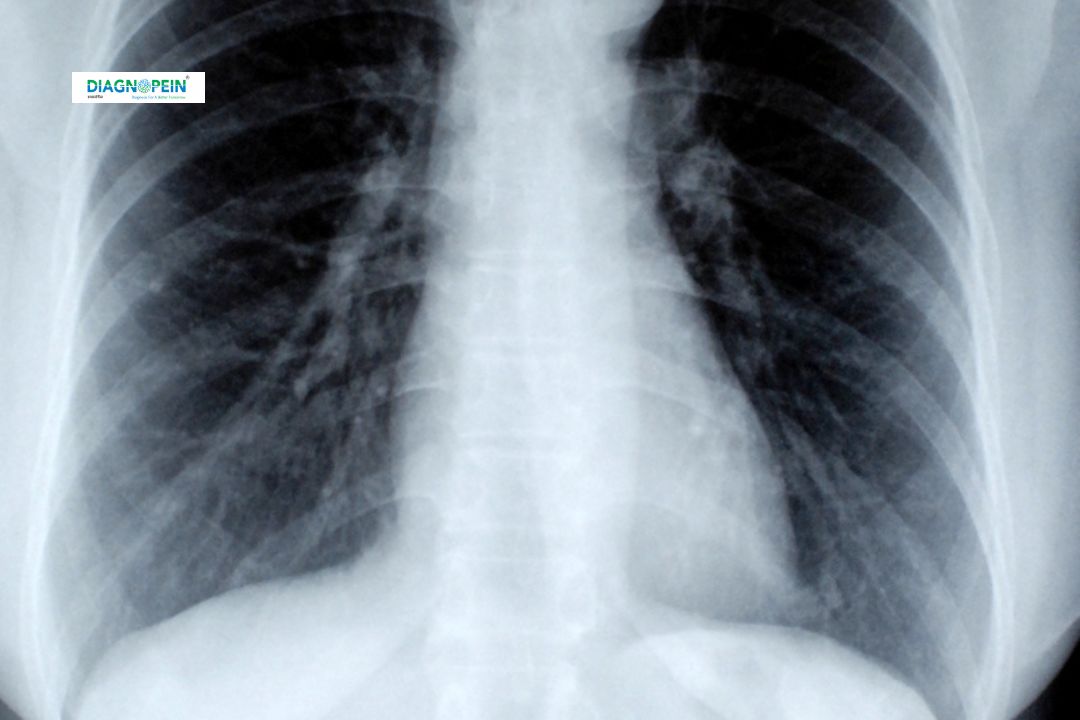

At Diagnopein Karad, the X-Ray Chest 6x8 test is one of the most essential and commonly performed radiological investigations used to evaluate the condition of the lungs, heart, and chest wall. This diagnostic imaging technique uses low levels of ionizing radiation to produce clear black-and-white images of the chest area.

Doctors often recommend an X-Ray Chest 6x8 when symptoms like chronic cough, chest pain, shortness of breath, or fever persist for an extended period. It helps detect and monitor a wide range of conditions such as pneumonia, tuberculosis, lung infections, heart enlargement, rib fractures, and other thoracic abnormalities.

Radiologists at Diagnopein Karad evaluate lung fields, cardiac silhouette, costophrenic angles, ribs, and diaphragm contours to ensure every detail is analyzed thoroughly.